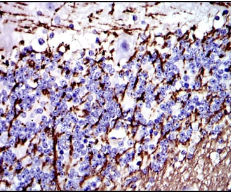

IHC    1/200 - 1/1000